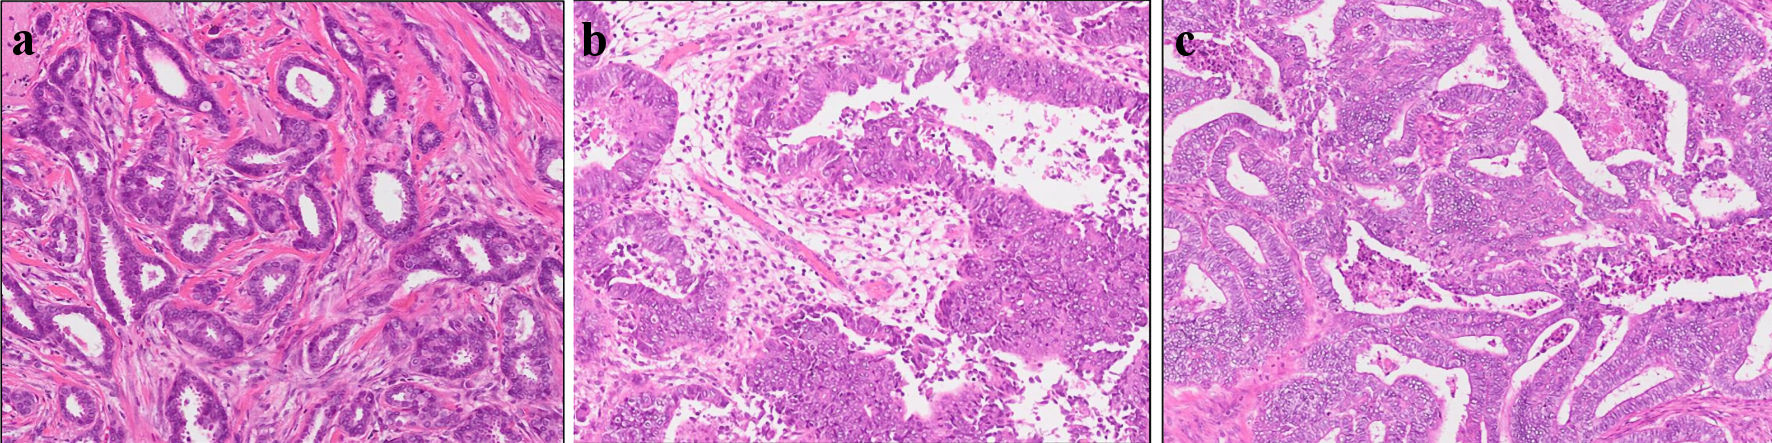

This is a case of a 42-year-old woman with hypothyroidism as comorbidity. The family history revealed that her mother had lung cancer, her paternal aunt had breast cancer, her paternal uncle had pancreatic cancer, and her maternal uncle had prostate cancer and malignant lymphoma. She presented with a left breast mass with pain. A core needle biopsy of breast mass showed invasive ductal carcinoma (IDC). After several examinations, such as computed tomography (CT) and magnetic resonance imaging (MRI), she was diagnosed with 13 × 13 mm breast cancer (cT1N0M0) and underwent breast-conserving surgery with sentinel lymph node biopsy. Pathological analysis showed 12 × 10 mm of IDC with nuclear grade 1, estrogen receptor (ER)-positive, progesterone receptor (PgR)-positive, and human epidermal growth factor receptor 2 (HER2)-negative (pT1N0M0, stage I) (Fig. 1a). She received adjuvant radiotherapy (50 Gy) and endocrine therapy (tamoxifen). At the age of 45 years, the follow-up CT scan revealed a tumor in the uterus (Fig. 2a). She was diagnosed with endometrial cancer and underwent a laparoscopic modified radical hysterectomy with bilateral oophorectomy with pelvic lymph node dissection. Pathological analysis showed localized endometrioid adenocarcinoma, exophytic type, ly0, v0, margin (-), grade 1 (pT1aN0M0) (Fig. 1b). Then she received six cycles of adjuvant chemotherapy, combined with paclitaxel and carboplatin. One year after, the follow-up CT scan revealed multiple intraabdominal masses (Fig. 2b). As peritoneal dissemination from breast or endometrial cancer was suspected, laparoscopic peritoneal dissemination resection was performed. Pathological analysis of peritoneal tumor confirmed the dissemination of endometrioid adenocarcinoma (Fig. 1c). Ten years after breast cancer surgery, mass lesions were noticed in her thoracic cavity on a follow-up CT scan (Fig. 3a). The positron emission tomography-computed tomography (PET-CT) scan showed an accumulation of maximum standardized uptake value (SUVmax) = 2.5 (Fig. 3b). Video-assisted thoracoscopic surgery was performed to identify the primary lesion of this tumor. The pathological analysis revealed the tumor positive for ER, PgR, and GATA binding protein 3 (GATA-3), which led to the diagnosis of metastasis from breast cancer (Fig. 3c).

![]() Click for large image | Figure 1. Histopathological results. Pathological analysis of surgical tissue from (a) breast, (b) uterus, and (c) abdominal tumor. |